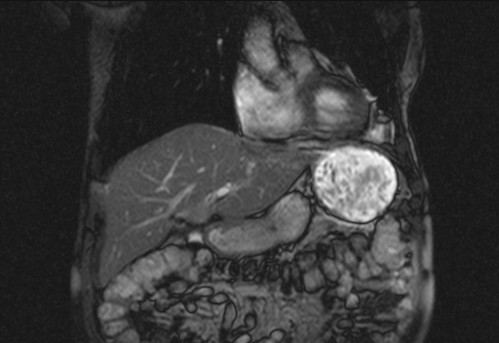

Auffälliges Abdomen bei der Vorsorgeuntersuchung einer älteren Dame

ICD: C64